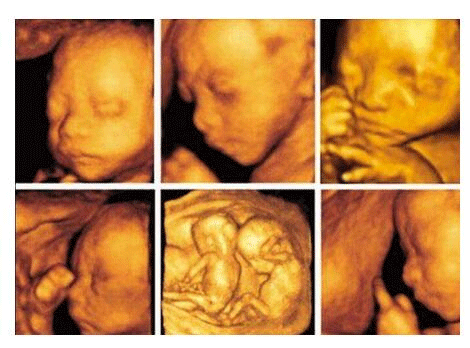

三维彩超,即彩色多普勒超声检查的一种,检查图像呈土黄色,通过多普勒超声仪器发出超声波,对体内各项器官进行成像。三维即其图像是立体的,可以更直观的看到器官的形态,及时发现病变并进行治疗。三维彩超常用于产检,用来判断胎儿的生长发育的情况或是否出现畸形等。

产检中,三维彩超通过测量子宫纵径、子宫体横径、子宫前后径这三条径线来观察胎儿是否正常。以及通过三维立体的成像,可以清晰的显示出胎儿各个内脏器官,以及面部器官、四肢的情况,来简单的判断胎儿是否存在畸形,包括胎儿是否患有先天性心脏病也是能够检查出来的。

24周的胎儿,其身体结构的生长发育已经很完善了,且胎儿大小也很合适,这时候做三维彩超可以很直观的看到胎儿的五官四肢、以及内脏器官,还能了解胎儿双顶径、头围、腹围、股骨长等发育情况。

2、清晰度不同

目前临床上维彩超检查是直接对胎宝宝先天头面部畸形的判断,可以拍到宝宝生长发育的局部立体图像。而四维相对于三维来说,会更清晰,对胎宝宝畸形,如唇腭裂、四肢发育畸形、脑膜膨出、脊柱裂、腹壁裂和心血管畸形等能够做早期诊断,并且能够立体显示胎宝宝的颜色、各器官的发育情况,甚至在母体内吸吮、睡觉等动态也可以捕捉到。。